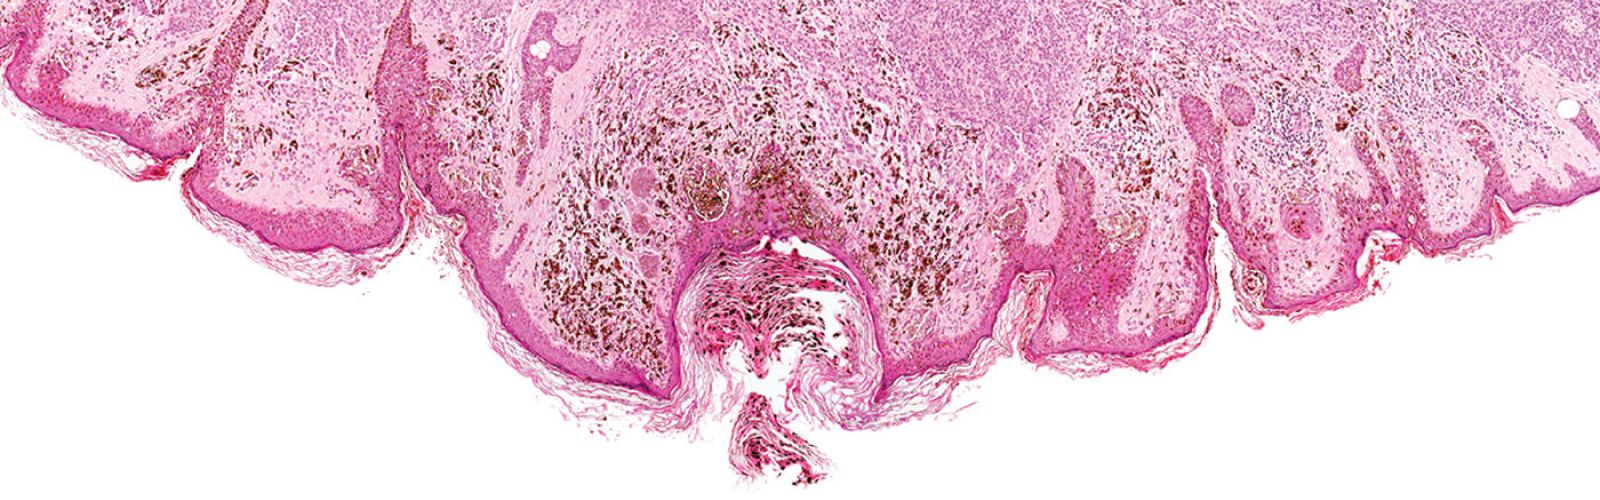

Melanomas are naturally heterogeneous tumors, with different subpopulations of cells that differ in aggressiveness and response to therapy. This heterogeneity is observed between patients and even within the same patient and represents an obstacle for immunotherapy success.